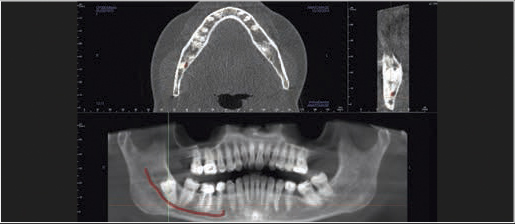

Pole obrazowania 8 x Ø15 cm obejmujące swoim zasięgiem SSŻ, szczękę oraz żuchwę oraz przekrój zatok przy wykorzystaniu dawki porównywalnej z panoramicznym obrazem 2D.

Tomografia cyfrowa z jeszcze bardziej innowacyjną technologią Dose Reduction Technology™ (DRT) urządzenia GXDP-800 CBCT umożliwia wykonywanie zoptymalizowanych obrazów rentgenowskich 3D / tomograficznych przy zastosowaniu małej dawki promieniowania RTG. Zmniejszenie dawki promieniowania to istotna korzyść w określonych przypadkach klinicznych takich jak obrazowanie pooperacyjne, wstępne planowanie wszczepienia implantu czy obrazowanie RTG u dzieci.

Cztery różne pola obrazowania zapewniają niezawodną diagnostykę 3D w całym obszarze jamy ustnej. Zapewniają one precyzyjne dopasowanie, odpowiednie do wskazań a także uniwersalne możliwości zastosowania w codziennej praktyce – od endodoncji, poprzez implantologię do chirurgii jamy ustnej.